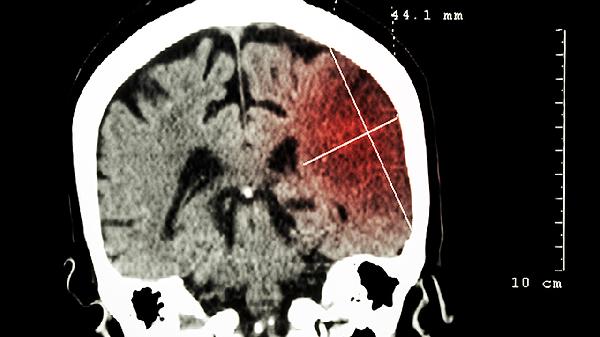

40歲以上人群建議每年進(jìn)行頭顱CT檢查,早期發(fā)現鈣化灶。若出現睡眠障礙、晝夜節律失調等癥狀,可檢測血清褪黑素水平。對于已存在微小鈣化灶者,每6個(gè)月復查對比變化,必要時(shí)進(jìn)行磁共振波譜分析評估代謝狀態(tài)。